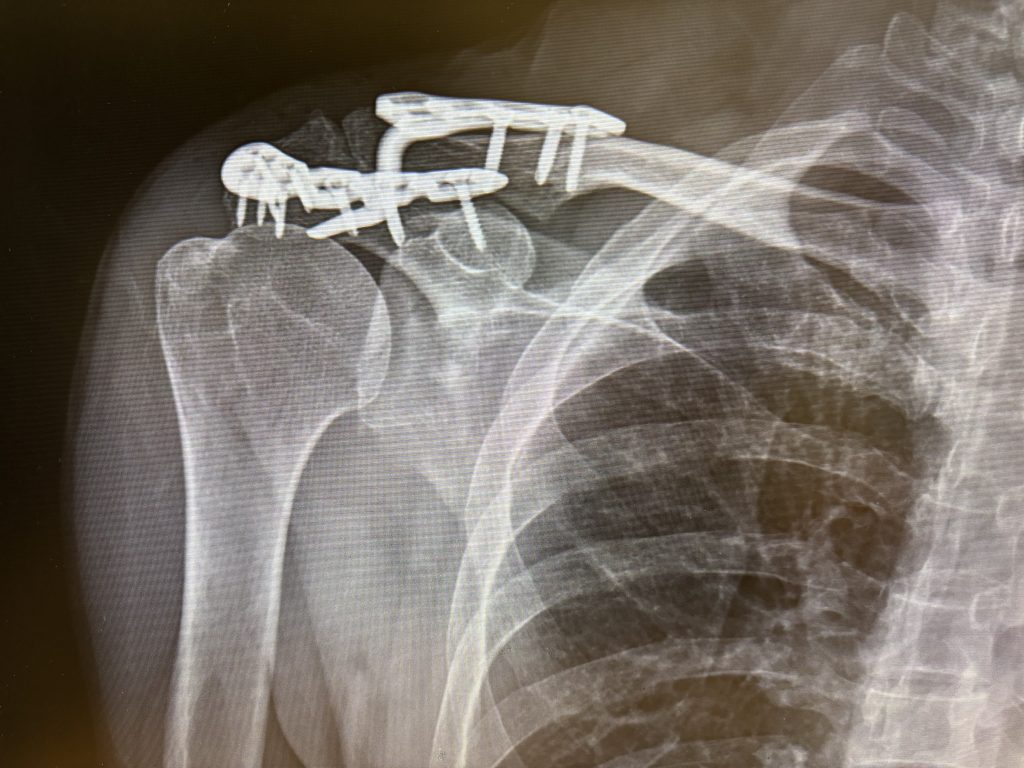

熱愛三鐵運動的60歲林姓男子騎公路車上山訓練,回程下坡時為閃避路邊竄出小貨車「犁田」,肩膀撞擊地面造成肩峰骨折及肩峰鎖骨韌帶斷裂,住院手術植入鉤狀鋼板固定,術後經3個月復健治療,重拾騎車樂趣。醫師提醒,騎自行車除了摔車創傷外,姿勢不當、肌肉過度施力也可能造成「自行車病」的運動傷害。